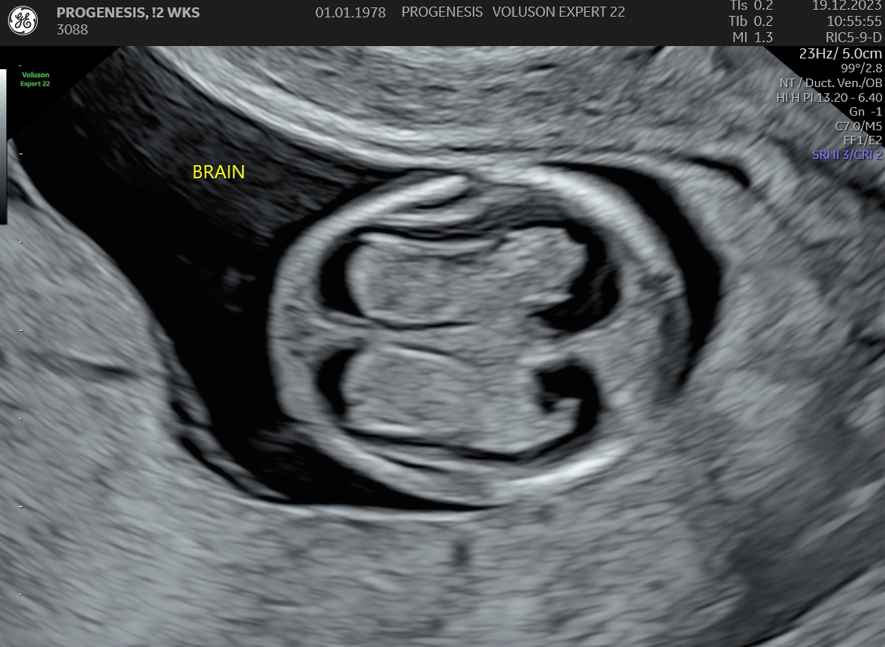

Υπερηχογράφημα Αυχενικής Διαφάνειας (11-14 εβδομάδων)

Το υπερηχογράφημα της αυχενικής διαφάνειας, πραγματοποιείται από τις 11 εβδομάδες +1 ημέρα έως 13 + 6 ημέρες κύησης και σε μήκος εμβρύου από 45mm έως 84mm.

Διάγνωση ανατομικών ανωμαλιών

Πολλές και σημαντικές ανωμαλίες, όπως ανεγκεφαλία, απουσία άκρων, ομφαλοκήλη, ορισμένες συγγενείς καρδιοπάθειες και άλλες ανωμαλίες, είναι ορατές απ' αυτό το στάδιο της κύησης. Δίνουμε ιδιαίτερη έμφαση στην αξιολόγηση της καρδιάς των εμβρύων, τόσο για την αξιολόγηση χρωμοσωμικών ανωμαλιών όσο και πρώιμη ανίχνευση συγγενών καρδιοπαθειών από το 1ο κιόλας τρίμηνο (π.χ. υποπλασία καρδιάς, συγγενή μετάθεση μεγάλων αγγείων).